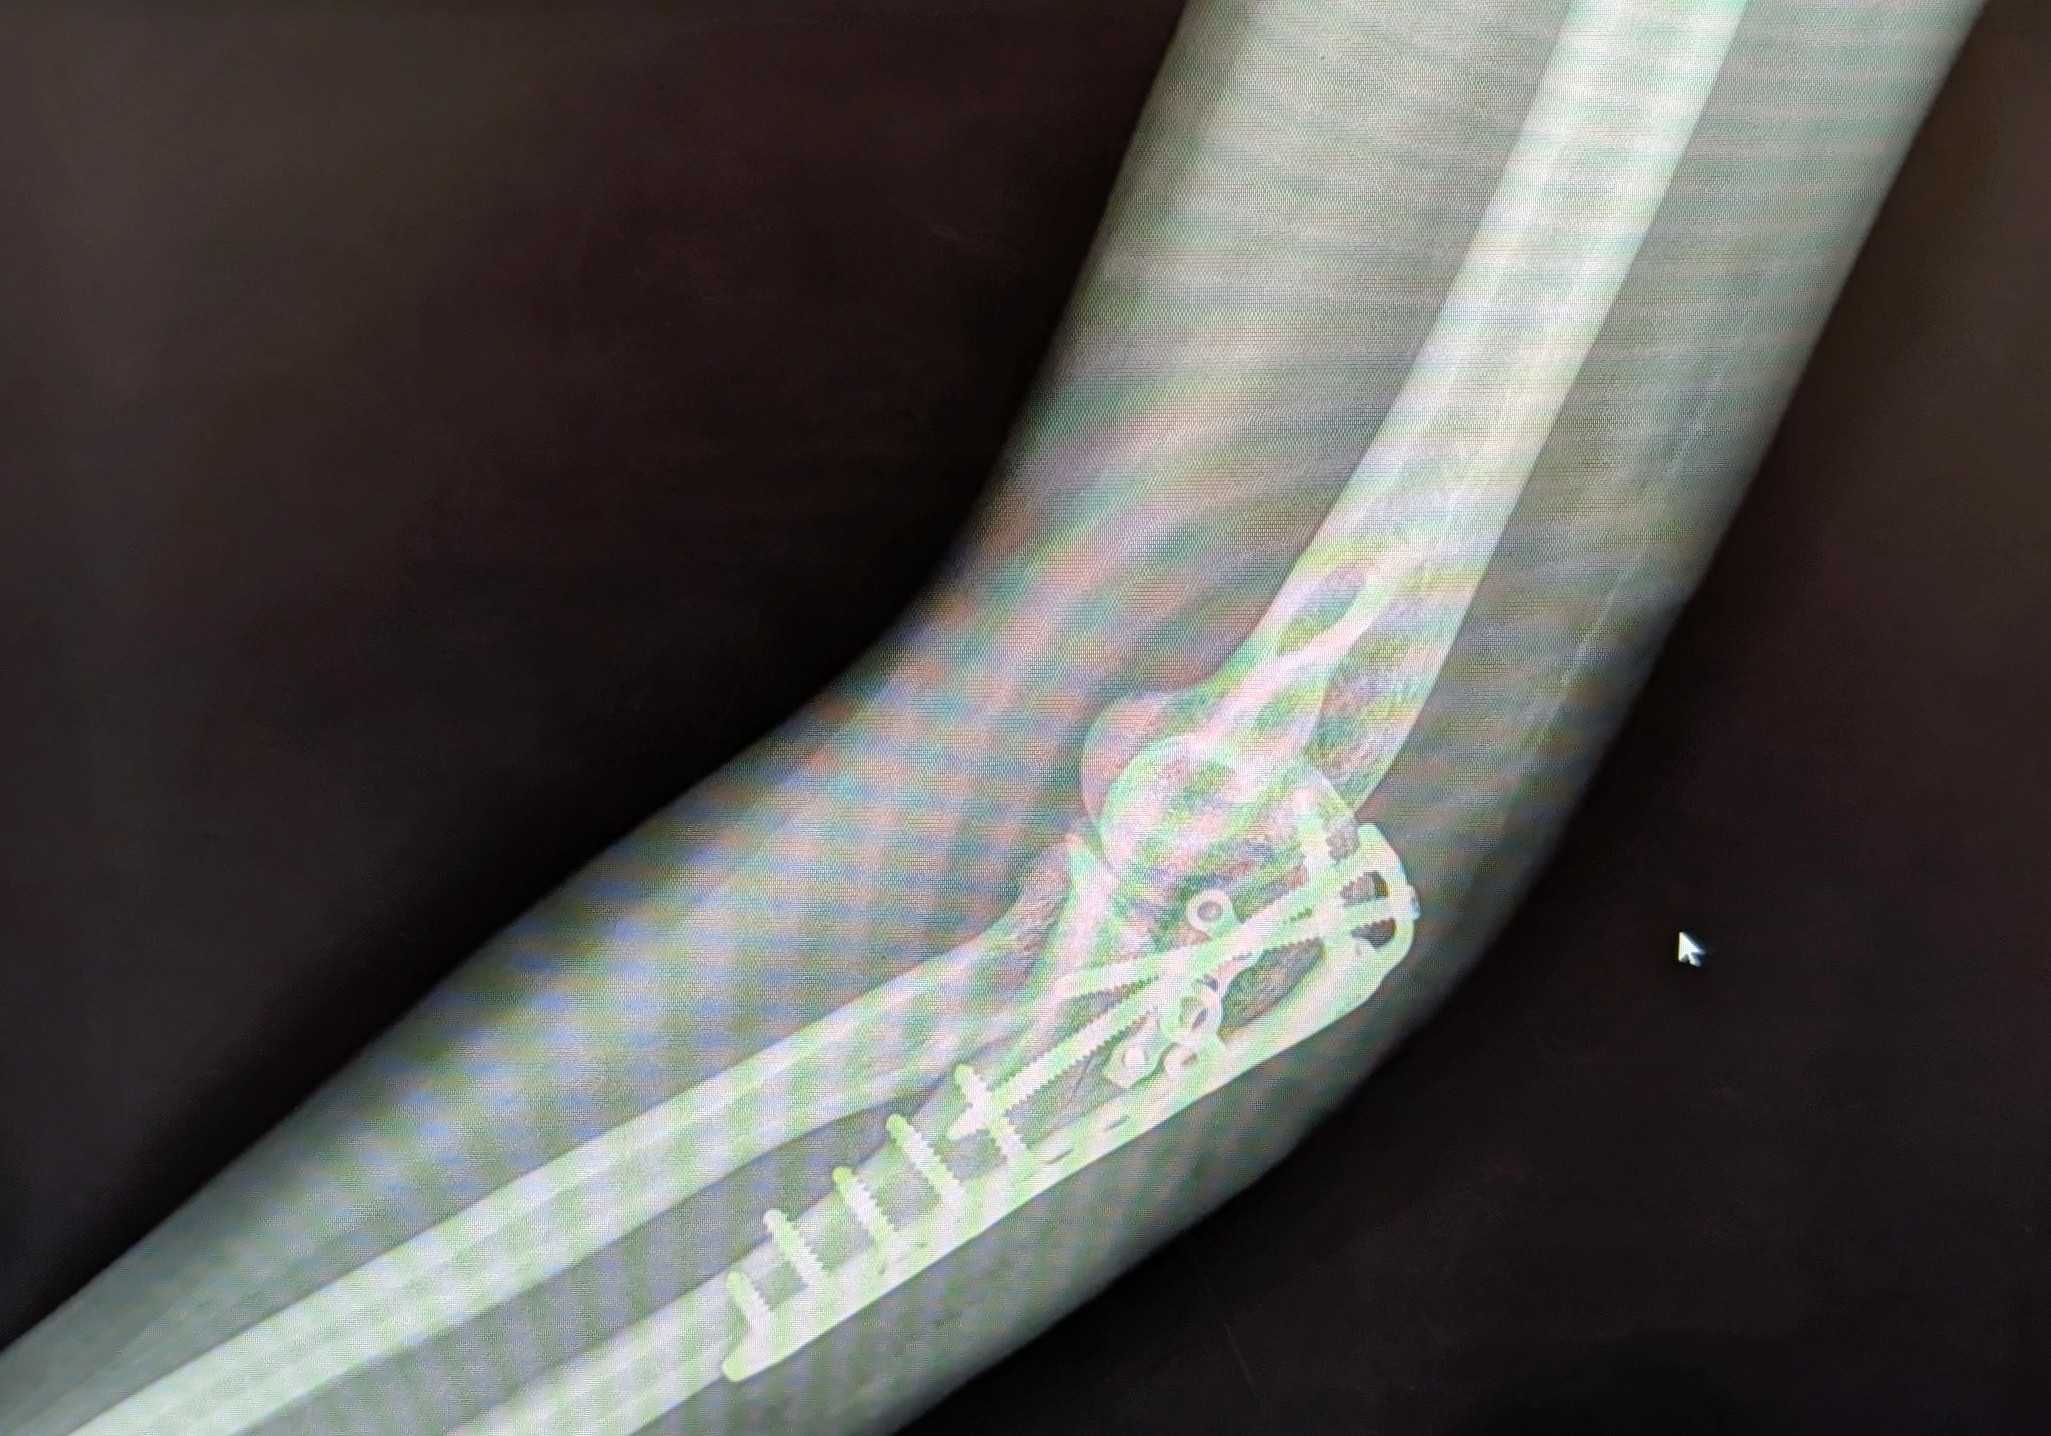

All my new hardware